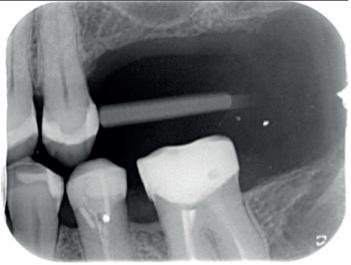

Een 48-jarige gezonde vrouw presenteerde zich in de nazorgfase 2 jaar na initiële behandeling met pockets van 6–7 mm en furcatieproblematiek bij de 47 en 46 (afbeelding 1.1 en 1.3). Bloeding bij sonderen was aanwezig, maar de patiente wilde geen chirurgische behandeling. Ze hield er een keurige mondhygiëne op na en kwam trouw iedere drie maanden voor nazorg.

De pockets werden onder lokale anaesthesie behandeld met een combinatie van ultrasoon en handinstrumentarium volgens de hierboven beschreven methode. De natriumhypochloriet/aminozuur-gel werd vijfmaal aangebracht en na iedere applicatie mechanisch verwijderd. Daarna werd de pocket gevuld met cross-linked hyaluronzuur.

Na 6 maanden was de pocketdiepte teruggebracht tot 3 mm en was er geen bloeding na sonderen waarneembaar. Een recessie van 2 mm was aanwezig. Röntgenologisch was er nieuw bot zichtbaar (afbeelding 1.2 en 1.4).